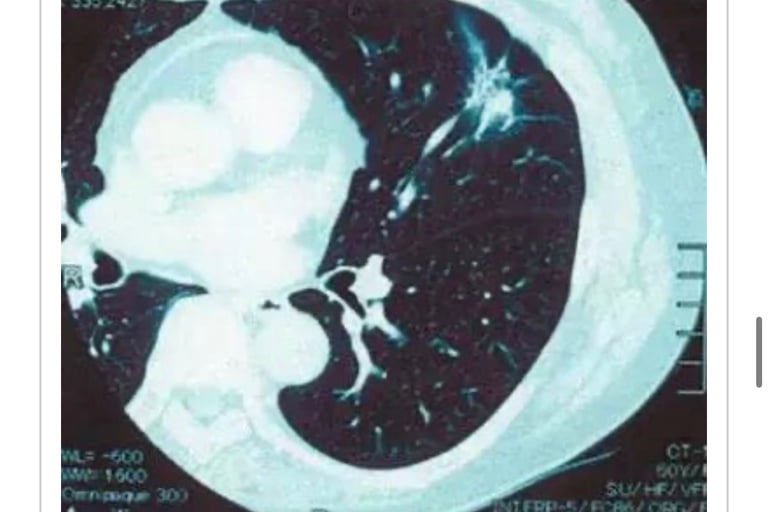

F・T(1941年生、男性)2004年6月患者左肩疼痛、05年1月出现声带麻痹、颈部以及锁骨下淋巴肿大,通过PET发现纵隔肿瘤。2005年5月12日来我院就趁。

05年6月30日MW照射治疗开始。

05年7月19日开始NK・T细胞免疫疗法,2周一次3个月一疗程。

同时从7月17日至9月20日放疗。MW照射到05年12月为止合计37次。

2006年11月PET检查无异常。

从05年2月至06年4月,肿瘤标志物CEA从10.3ng/mℓ恢复到正常指标(表1)。

2008年3月26日确认再发后,连续接受放射治疗30次、化疗4个疗程。组织学检测结果为小细胞癌。

2008年9月24日NK・T细胞免疫疗法和MW照射治疗再开始。至2010年9月照射合计31次。

2012年3月CT成像结果无异常。